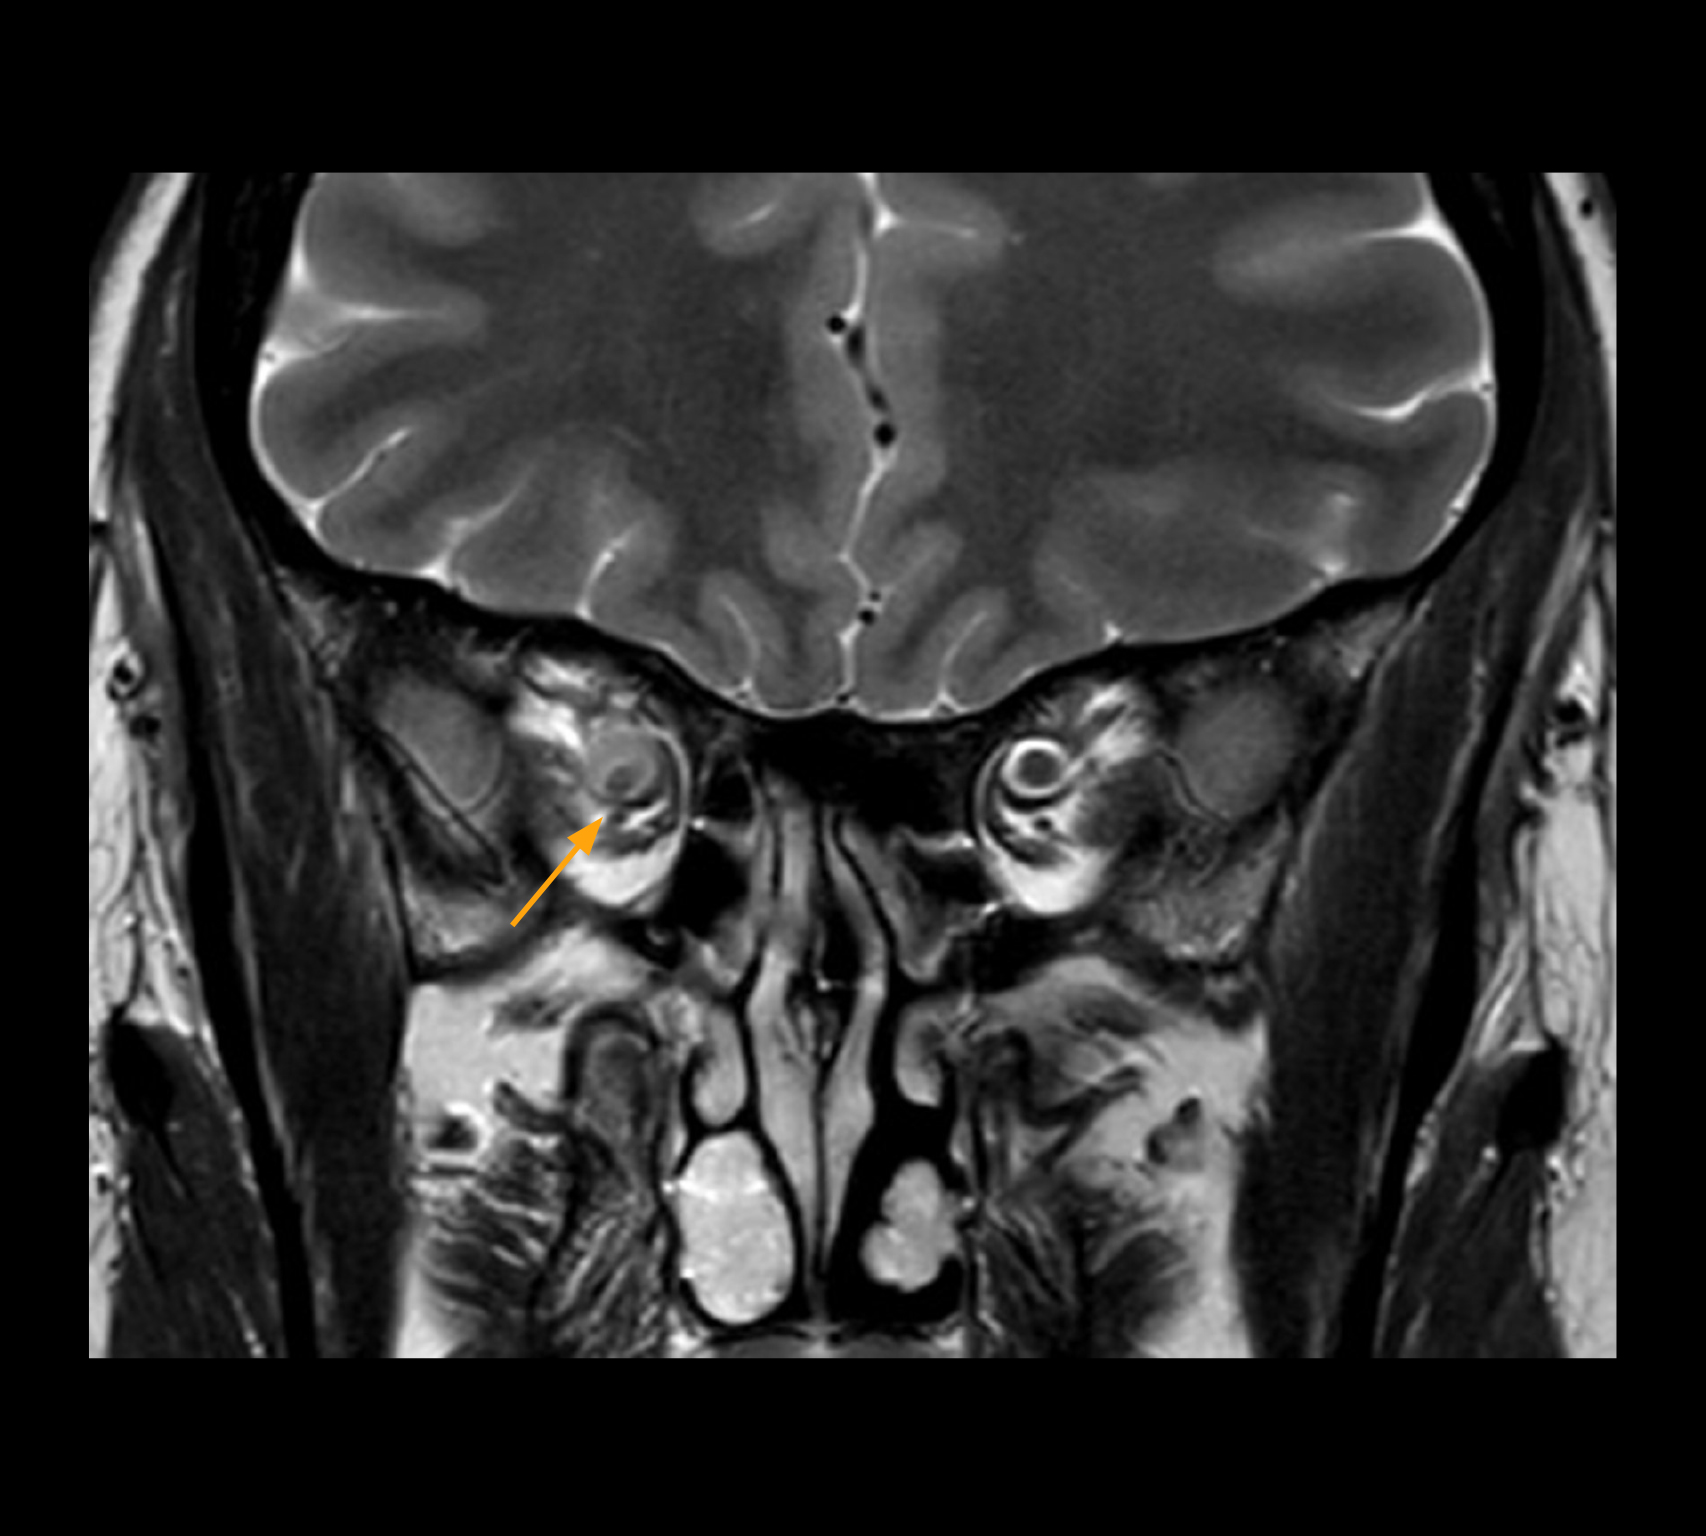

In select cases, the MR 7700 has helped the hospital’s physicians more clearly visualize pathology. “We’re definitely getting the impression that tumors are better delineated with the MR7700,” Dr. Heindel says. “For example, I examined a patient who had been diagnosed in another hospital with possible neuritis of the optic nerve. However, the MR 7700 images allowed me to diagnose it as an optic nerve sheath meningioma, a rare and often misdiagnosed, slowly growing tumor that wascausing the visual disturbances in the patient. The lesion was so well delineated on the high resolution MR 7700 images that our neurosurgeon decided he did not need a biopsy before proceeding directly with decompression of the optic canal and peeling away those tumor cells.”

High-resolution MRI impressively demonstrates the compression and narrowing of the right optic nerve in this case of optic nerve sheath meningioma (ONSM). The coronal T2-weighted images show the hyper-intense, half-moon shaped lesion, that is clearly visible in the axial T1W image after contrast injection (right). These imaging findings were so convincing that there sponsible neurosurgeon did not consider a pretherapeutic histological clarification.

High resolution-MRI impressively demonstrates the compression and narrowing of the right optic nerve in this case of optic nerve sheath meningioma (ONSM). The coronal T2-weighted images show the hyper-intense, half-moon shaped lesion, that is clearly visible in the axial T1W image after contrast injection (right). These imaging findings were so convincing that there sponsible neurosurgeon did not consider a pretherapeutic histological clarification.